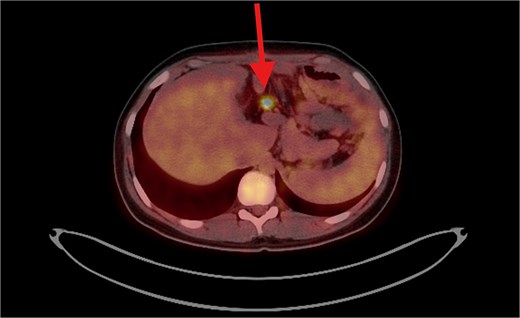

PET/CT scan shows a clear surgical site (left subphrenic area) with no residual/recurrent mass, but there are multiple peritoneal and mesenteric nodules which appear to be hypermetabolic on PET scan, suggesting secondary metastasis.